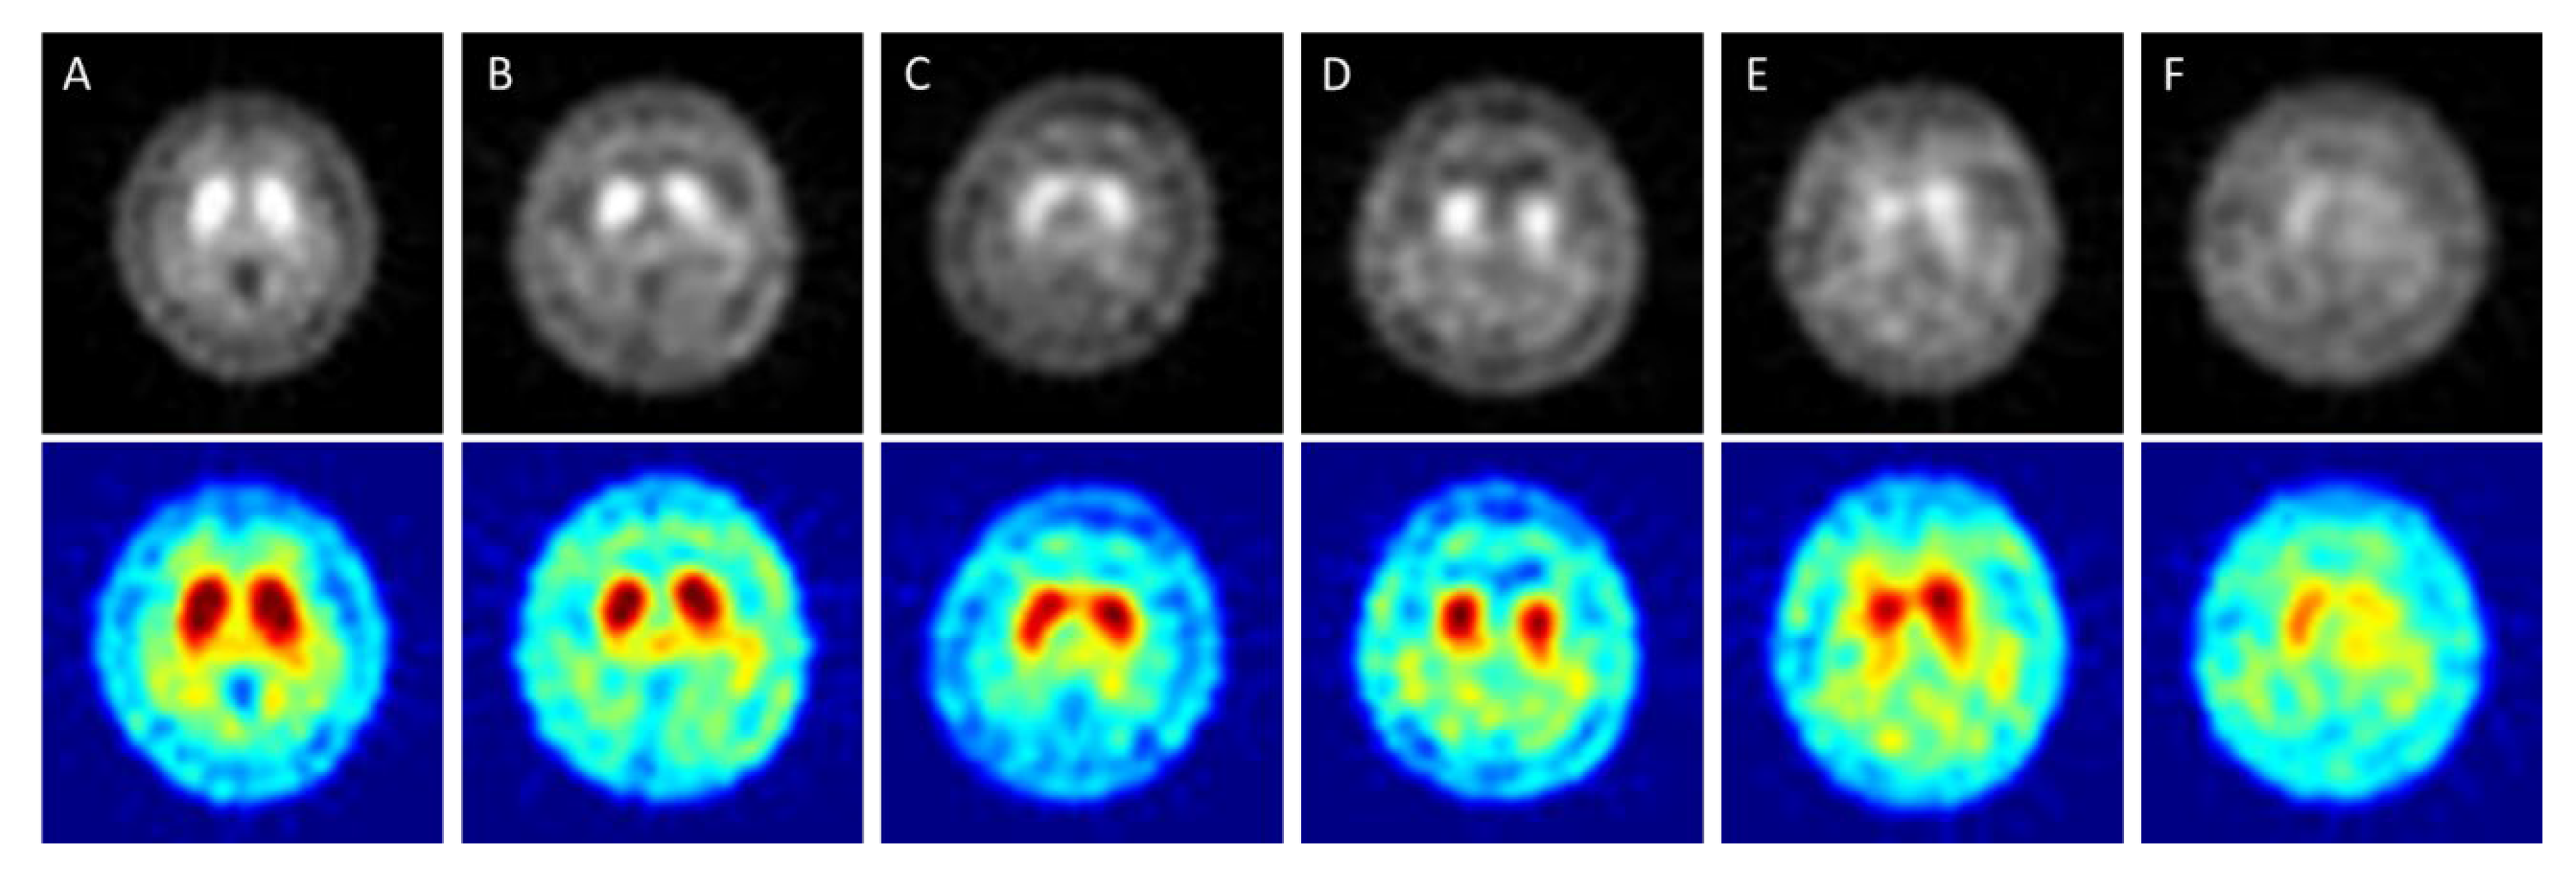

Classification of the Multiple Stages of Parkinson’s Disease by a Deep Convolution Neural Network Based on 99mTc-TRODAT-1 SPECT Images

2.2. The Imaging Conditions of 99mTc TRODAT-1 SPECT

- When using deep convolutional neural network technology to classify 99mTc-Trodat-1 PD images for the original grayscale images processed through five pre-trained models (AlexNet, GoogLeNet, VGG19, ResNet, DenseNet201) the highest accuracy was 0.83 for AlexNet. In six categories (healthy, HYS I~V), the best accuracy was 0.78 obtained by VGG19 in four categories (healthy, early, mid, late);

- For color images, DenseNet201 yielded the highest accuracy of 0.85 in four categories. In six categories, the highest accuracy was 0.78 also obtained using DenseNet201;

- Overall, the pre-trained models could produce accurate results when using grayscale images. In this case, the pseudocolor images might be non-essential;